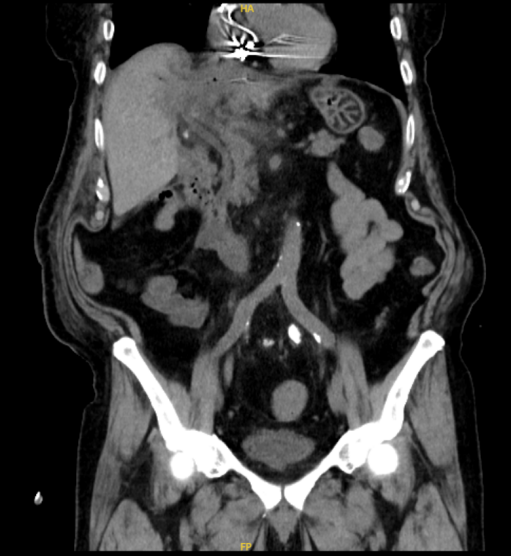

最近,一名81岁的男性患者因为“右上腹疼痛不适1周”就诊,入院查体发现皮肤、巩膜黄染,经过进一步检查,考虑腹痛原因为胆囊炎和肝巨大囊肿(图1,肝囊肿最大径18cm),巨大肝囊肿压迫肝脏内胆管,还导致了梗阻性黄疸,即皮肤、巩膜黄染。经过充分的术前评估,我们为该患者做了腹腔镜下胆囊切除和肝囊肿开窗术,术后患者的症状完全缓解,复查肝囊肿消失(图2)。体检发现肝囊肿,对于许多人来说可能是一个令人担忧的消息。然而,肝囊肿其实是一种常见的肝脏良性病变,大多数情况下并不需要过度担心,像上述患者的情况是比较少见的。本文将详细解释肝囊肿的相关知识,包括其分类、病因、症状、诊断、治疗以及预防等方面,帮助大家更好地理解和应对这一疾病。

图2